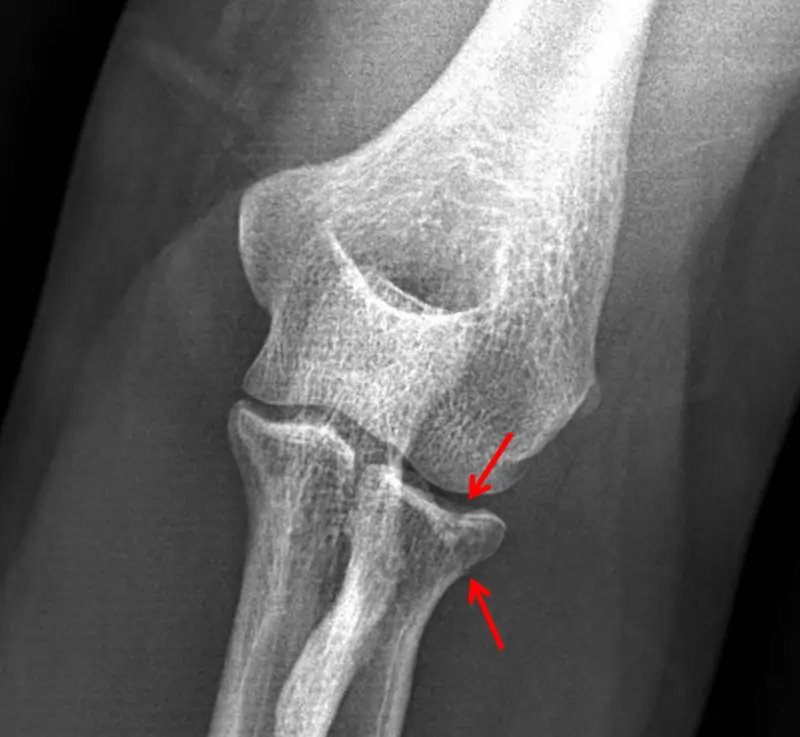

Diagnostic Procedures

The preliminary diagnostic tool used for determining radial head fractures is a radiograph. Mason Type 1 fracture do not ever show

on X-ray. In such circumstances, a ‘sail sign’ might mean a fracture. A ‘sail sign’ is a silhouette on a radiograph driven by an enlarged fat pad at the elbow. Recent investigations are glancing at the use of sonography in seeing occult fractures more fast. Existing diagnostic processes can take upward of three weeks before the determination of a fracture.